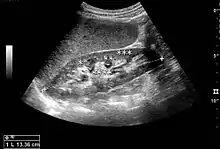

Figure 1. Normal adult kidney. Measurement of kidney length on the US image is illustrated by ‘+’ and a dashed line. *Column of Bertin; ** pyramid; *** cortex; **** sinus.[1]

The length of the adult kidney is normally 10–12 cm, and the right kidney is often slightly longer than the left kidney. The adult kidney size is variable due to the correlation with body height and age; however, normograms for pediatric kidney size are available.[1]

Cortical thickness should be estimated from the base of the pyramid and is generally 7–10 mm. If the pyramids are difficult to differentiate, the parenchymal thickness can be measured instead and should be 15–20 mm (Figure 3). The echogenicity of the cortex decreases with age and is less echogenic than or equal to the liver and spleen at the same depth in individuals older than six months. In neonates and children up to six months of age, the cortex is more echogenic than the liver and spleen when compared at the same depth.[1]